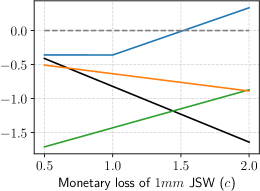

As the cost-related parameters, and , are key factors in our reward function, we aimed to quantitatively assess their impacts on our method. Specifically, we conducted two experiments involving our proposed methods, CLIMATv2, ANS, and NS policies. In the first experiment, we varied the hospital visit cost, , while keeping the MLAC, , unchanged. In the second experiment, we reversed the settings.

We present the results of the first experiment in Figure 4a, demonstrating the association between and the RPP over year, with a fixed of . Generally, all methods exhibited a decreasing trend in the reward as the hospital visit cost increased. Compared to the mentioned baselines, our RL-based method, corresponding to the blue curve in Figure 4a, consistently gained better rewards per person with every value of . The NS policy, displayed in black, resulted in a constant reward of per person since no follow-up data was acquired. Increasing from to caused a significant drop of approximately in the RPP of the ANS policy. Our proposed method met the ANS policy at and approached the NS policy when increased.

We demonstrate the results of the second experiment in Figure 4b. The performance of CLIMATv2 and the NS policy exhibited a decreasing trend as the JSW cost, , increased while keeping unchanged . In contrast, we observed that the ANS policy generally increased in proportion to . Our policy achieved a constant reward of for , and demonstrated a linear increase for . Overall, our proposed policy gained the highest reward among the methods at any value of . For values of greater than , our method stands out as the sole approach yielding positive rewards per person.

To gain deeper insights into the trade-offs related to the cost parameters and , and their impact on the outcomes, we investigated the relationship between the relative cost and the resulting RPP normalized over the hospital cost, . Specifically, we varied the hospital visit cost parameter, , across the range , while adjusting the MLAC, , within the set . The association is illustrated in Figure 4c. We observed that exhibited an inverse, non-linear relationship with the increasing of . In other words, decreasing was beneficial for the resulting RPP. Specifically, when the ratio declines to , it becomes the critical trade-off point at which our policy begins to yield positive RPPs. The raw experimental data behind Figure 4c is shown in Suppl. Table S2